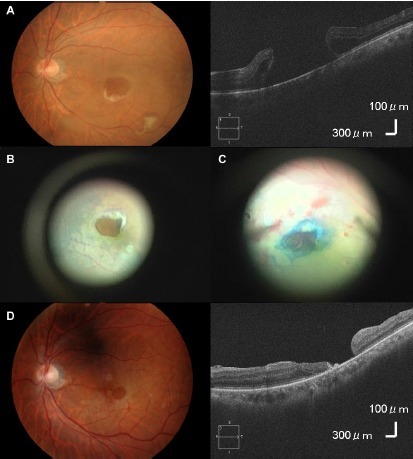

眼底检查显示左眼黄斑颞侧马蹄形裂孔(图 1A),裂孔大小为 0.75 视盘直径(DD),视网膜裂孔与玻璃体并没有粘连。荧光造影显示左眼有无灌注区,无视网膜静脉阻塞(图 1B)。OCT 显示左眼视网膜脱离累及中心凹(图 1C)。右眼无明显异常。

图 1 A 为眼底检查显示左眼黄斑颞侧马蹄形裂孔;B 为荧光造影显示左眼有无灌注区,无视网膜静脉阻塞;C 为 OCT 显示左眼视网膜脱离累及中心凹

拟于 2 周后行左眼玻璃体手术,几天后,黄斑裂孔上皮瓣消失,黄斑裂孔大小增大为 1.5DD(图 2A,B)。

患者行玻璃体手术,手术方法类似巨大黄斑裂孔(MH)手术。为关闭裂孔,行内界膜撕除联合 20%SF6 气体填充术(图 2C,D)。术后 1 月,裂孔周围视网膜连接,左眼视力达到 0.2。

图 2 A 为几天后,黄斑裂孔上皮瓣消失,黄斑裂孔大小增大为 1.5DD;B 为术前,黄斑裂孔大小为 1.5DD;C 为为关闭裂孔,行内界膜撕除联合 20%SF6 气体填充术;D 为术后黄斑裂孔大小减小为 0.5DD,黄斑裂孔闭合不完全